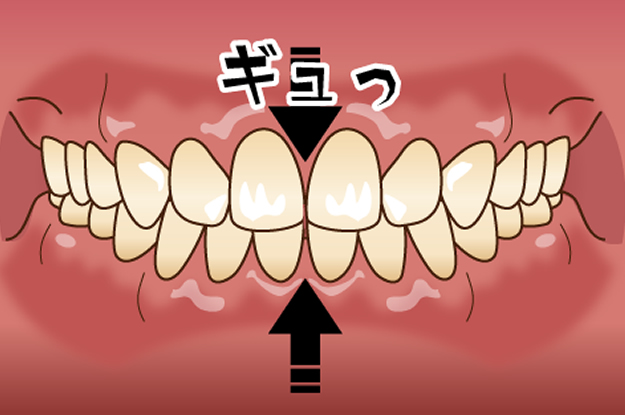

良く一般的に歯ぎしりと言われるもので、上下の歯をこするタイプで、ギリギリと音が出ます。クレンチング(食いしばり)

音を鳴らさずに歯を強くかみしめるタイプで、周りに気付かれる事が少ないです。このタイプの場合は特にグッとかみしめている事がありますので、筋肉の疲労が顕著にあらわれます。